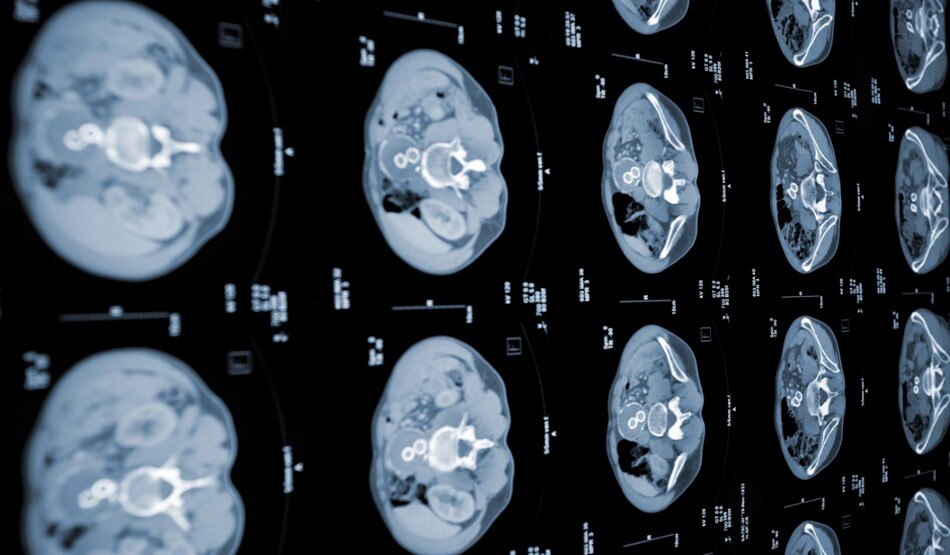

बिना सूजन के पेट का आकार इतना कैसे बढ़ गया फिर जल्दी से सीटी स्कैन किया और पता चला कि मरीज के पूरे पेट में काफी बड़ा ट्यूमर है. जिसका साइज 30x20x14 सेंटीमीटर है जो कि दो बड़े फुटबॉल के बराबर है और इसे सर्जरी के द्वारा ही निकाला जा सकता है.